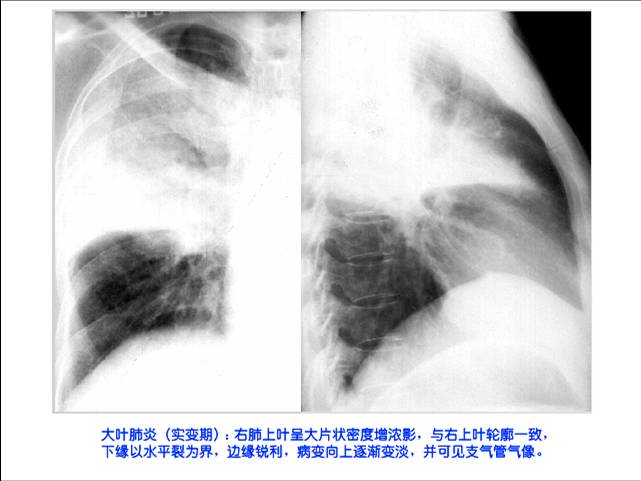

照片名称:大叶性肺炎

照片名称:大叶肺炎-消散期

照片名称:大叶肺炎-突变期